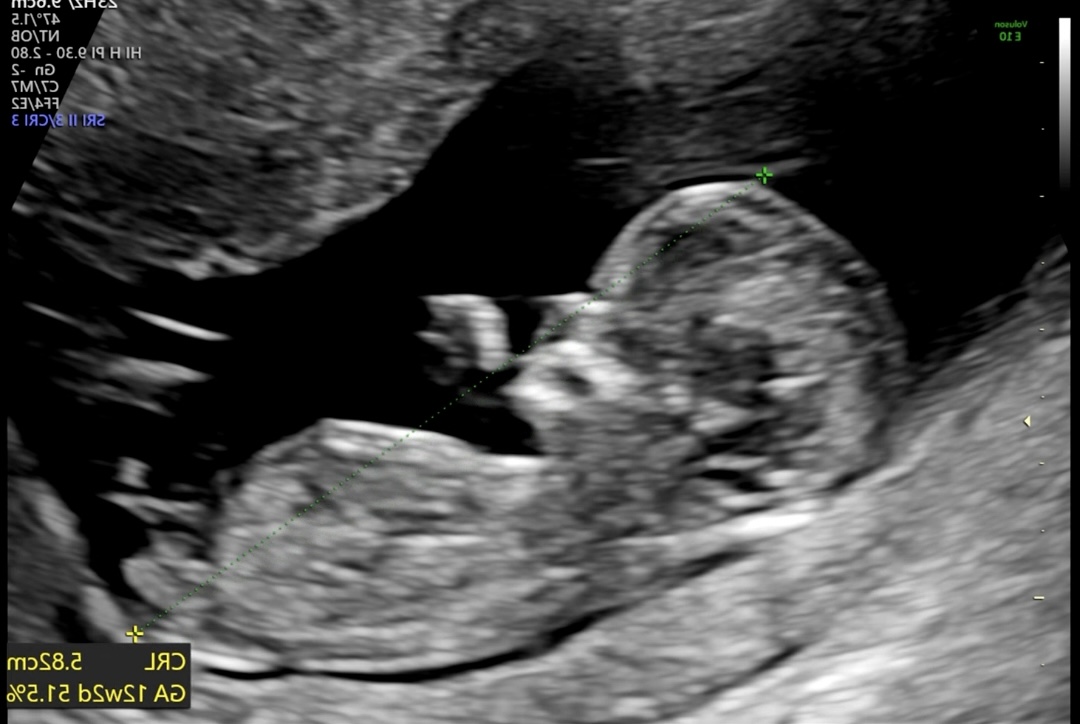

📸나의 12주차 초음파 사진과 장꾸맘의 예측

저는 임신 12주 차에 1차 기형아 검사를 하면서 초음파사진과 원본 동영상을 장꾸맘 카페에 올려서 각도법을 문의했어요!

장꾸맘 카페에 올리실 때 꼭 동영상 원본을 올리셔야 합니다^^

그리고 3일 정도 뒤쯤에 장꾸맘님께서 조심스럽게 아들에 한 표라고 하시더라고요